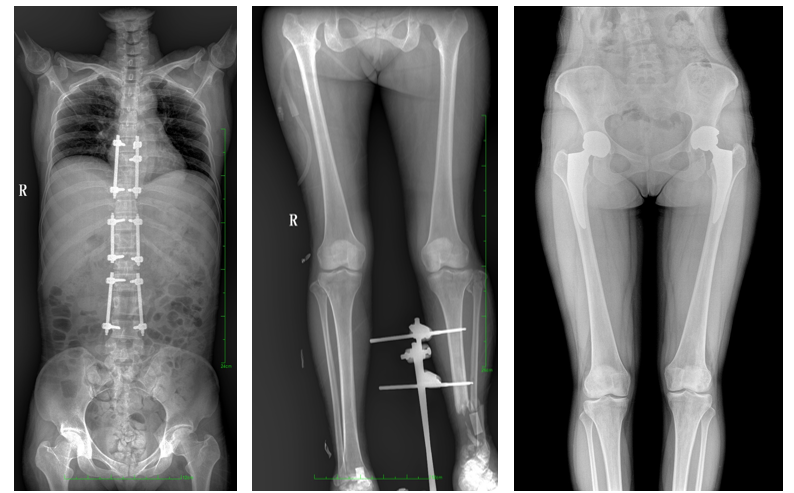

全脊柱一次成像 不拼接

17"*34"有效视野,是市面大尺寸平板的2倍,一次成像不拼接。相较于多张摄影再软件拼接的DR设备,PLX8600解决了拼接图像存在密度不均匀,拼接处图像配准和放大效应等问题,给临床带来了真正的大视野影像解决方案,高清画质,准确成像不失真,可一次性覆盖全脊柱或双下肢影像。PLX8600大视野平板动态DR摄影速度快,患者可以更快的完成检查,且单次摄影辐射剂量是常规多张摄影再软件拼接DR的1/2或1/3,低剂量给患者更多关爱。